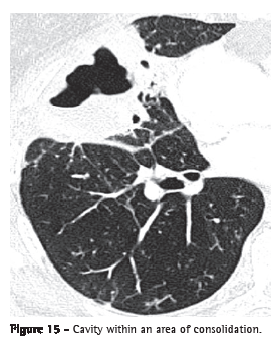

Cavitation (cavidade or escavação)

Cavities are gas-filled spaces, with or without air-fluid level, within a nodule, mass or pulmonary consolidation. They are typically produced by the expulsion or drainage of a necrotic part through the airway (Figure 15) or to the pleural space. The walls of a cavity are usually irregularly outlined and measure over 1 mm in thickness. The word "cavity" is not synonymous with "abscess". Although the term "cavitation" can be translated to Portuguese as cavitação or ­escavação, the term cavitação has a different meaning in Portuguese and therefore should not be used as a synonym for escavação in this context.(7)